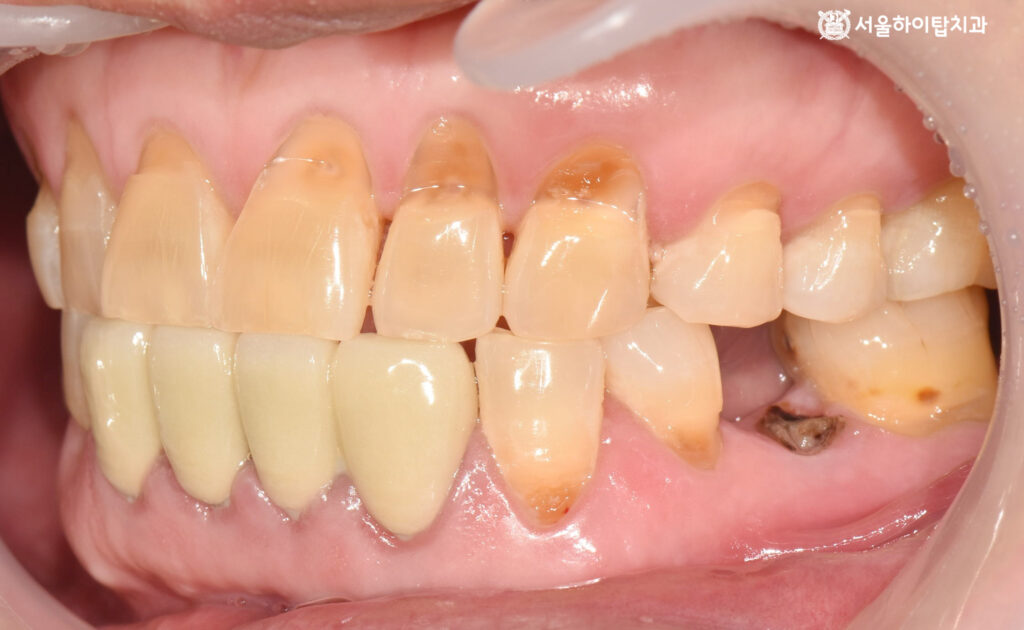

이어서 위에서 바라본 교합면을 살펴보면,

부평 치과 에서는 기존 보철치료가 완료된 아래턱 앞니를 제외하고,

위턱 앞니에서 진행 중인 마모를 뚜렷하게 확인할 수 있습니다.

또한, 뿌리만 남은 치아에서 충치가 진행 중임을 볼 수 있는데,

이는 잔존치근 상태에서 흔히 나타나는 소견입니다.

치관이 없어 청결 유지가 어렵고, 치근 부위에 세균이 쉽게 들어가

치근 우식, 염증, 주변 치조골 흡수를 유발할 수 있습니다.

정면에서 본 모습에서도 문제는 크게 달라지지 않습니다.

전반적으로 구강 내 잇몸 상태가 양호하지 않기 때문에,

균등한 저작 환경을 만들어 저작력 분산과 교합 안정을 확보하는 것이 필요합니다.